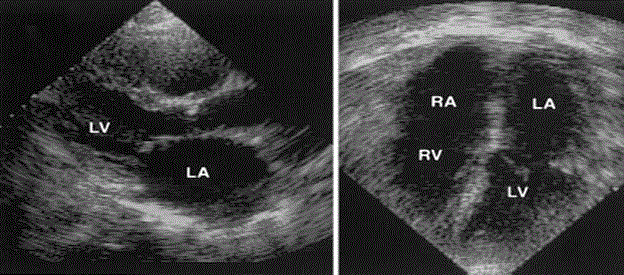

The availability and utility of standard echocardiography underlies the recommendation as the primary diagnostic imaging modality for RCM [86]. Echo findings in non-infiltrative RCM (idiopathic or RCM secondary to inflammatory cardiac disorders) show non-dilated, non-hypertrophied and normal contracting LV and large atrial dilation. Figure 4 illustrates echocardiography findings of a patient with idiopathic RCM, Parasternal long-axis view (left) and apical view (right) revealing non-dilated and non-hypertrophied ventricles but with dilated atria.

Figure 4: Standard Echo showing Morphological Features of Idiopathic RCM

Echo morphological features of a typical idiopathic RCM. Non-dilated, non-hypertrophied ventricle with dilated atria. Left, Parasternal long-axis view; right, apical view. LA indicates left atrium; LV, left ventricle; RA, right atrium; and RV, right ventricle. Adapted from Ammash et al. 2000, p. 2492 [6].